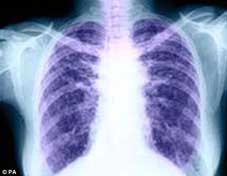

(CTO) - Ông L.T.P (69 tuổi, ở phường Ninh Kiều, TP Cần Thơ) bị đau ngực, khó thở gần 1 tuần, nhập viện Bệnh viện Đa khoa Hoàn Mỹ Cửu Long.

Bệnh nhân đau ngực 5 ngày, vào viện được phẫu thuật, ngăn nguy cơ suy tim